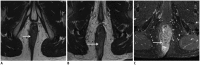

Although a rare disease, anal cancer is increasingly being diagnosed in patients with risk factors, mainly anal infection with the human papilloma virus. Magnetic resonance imaging (MRI) with external phased-array coils is recommended as the imaging modality of choice to grade anal cancers and to evaluate the response assessment after chemoradiotherapy, with a high contrast and good anatomic resolution of the anal canal. MRI provides a performant evaluation of size, extent and signal characteristics of the anal tumor before and after treatment, as well as lymph node involvement and extension to the adjacent organs. MRI is also particularly helpful in the assessment of complications after treatment, and in the diagnosis for relapse of the diseases.